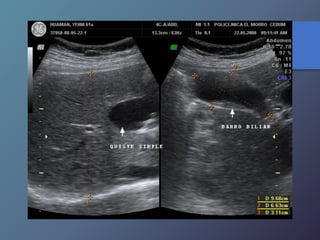

Quistes Simples

Características Ecográficas

• Imágenes anecoicas.

• Pared fina bien delimitada.

• Reforzamiento posterior.

Quistes Simples Características Ecográficas •Imágenes anecoicas. • Pared fina bien delimitada. • Reforzamiento posterior.